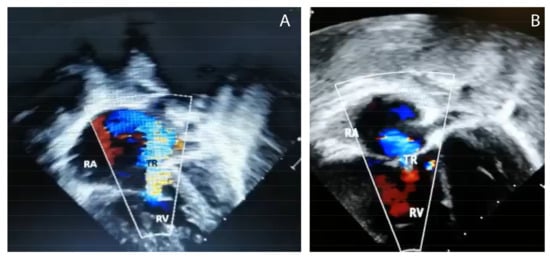

| Peak estimate of RVSP (mm Hg) | 82 | 74 | 60 | 67 |

| Resolution of PH by echocardiogram after thiamine | Improvement started by 4 h, resolution by 5 days. | Improvement by 3 h, resolution by 6 days. | Improvement started by 8 h, resolution by 7 days. | Resolution 5 days. |